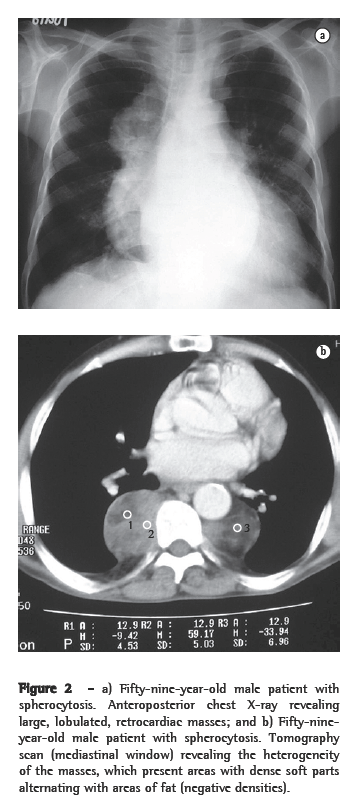

Of the six patients evaluated, four presented lower paravertebral masses. In three cases, the masses were bilateral and relatively symmetric, and, in one, the mass was unilateral (on the right). Regarding the content of the masses, the presence of adipose tissue was confirmed in three patients, and, in one of them, the quantity of adipose material was quite significant. In one patient, the masses were homogeneous, with dense soft parts (Figures 1a, 1b, 2a and 2b).

Thoracic involvement in EMH is rare.(1,5) When it occurs, it usually manifests as round, lobulated masses, with dense soft parts in the posterior mediastinum, being more common in the lower paravertebral regions.(1,2,4,5,9) Occasionally, those masses can appear in the anterior mediastinum or in the pleura.(4) Pleural effusion has been reported.(2,13) Four of our patients presented lower paravertebral masses, and two presented parietal pleural masses.

On CT scans, masses with dense soft parts, usually homogeneous, with characteristics similar to those described using conventional radiology,(1,2,5,6) and which might or might not be highlighted after administration of contrast material,(4,10) can be seen. This imaging method is important for analyzing the internal structure of the lesions, especially of those that are rich in fat,(5) in order to identify other paracostal masses, and for detecting bone alterations associated with certain hematologic diseases, such as thalassemia and sickle cell anemia.(6) In cases related to thalassemia, sickle cell anemia, or myeloid metaplasia, there can be widening of the medullary cavities of the ribs.(5) All of those aspects were identified in our cases. It is of note that two patients presented calcifications in the spleen, resulting from multiple infarcts, with autosplenectomy. Both of those patients had sickle cell anemia. This finding can also facilitate the differential diagnosis.

Active, recent lesions are richly vascularized, whereas old, inactive lesions have more adipose tissue and iron deposition. Between the two extremes, there are various combinations of findings, reflecting the different stages of evolution of the hematopoietic focus. Those histological differences are not represented on CT scans or MRIs. Recent, active lesions present dense soft parts on CT scans and intermediate signal intensity on MRIs (T1- and T2-weighted images). After administration of contrast material, there is usually some degree of impregnation in the active lesions. Old, inactive lesions can show increased density on CT scans, due to iron impregnation, or negative densities, due to adipose infiltration. On MRIs (T1- and T2-weighted images), old, inactive lesions can show high signal intensity, due to adipose infiltration, or low signal intensity, due to iron deposition.(4,8,12)